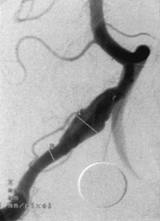

In the case of a fusiform aneurysm, the dilation in the blood vessel looks like a spindle. It is usually a complication of severe atherosclerosis, and is sometimes called an atherosclerotic aneurysm for this reason. Because of the elongated and tortuous shapes of fusiform aneurysms, “dolichoectasia” is another term that has been used to describe them. Diagnosis is performed with the assistance of medical imaging studies, which may include the use of contrast to clearly highlight the vascular system so that abnormalities can be clearly seen on the study.

Symptoms of a fusiform aneurysm vary. Their mass can compress surrounding structures, such as the brain stem. Any fibrofatty thrombus that they contain can fracture, flow through the circulation to other regions of the brain, and cause a stroke. Often, the issue is not identified in the early stages, with problems emerging when the aneurysm is close to rupture and the patient is experiencing symptoms associated with low blood pressure such as dizziness, fainting, and pale skin. The aneurysm may also be identified during medical imaging or routine screening for another medical issue. On imaging scans, these lesions appear as long, wide, serpentine shaped aneurysms.